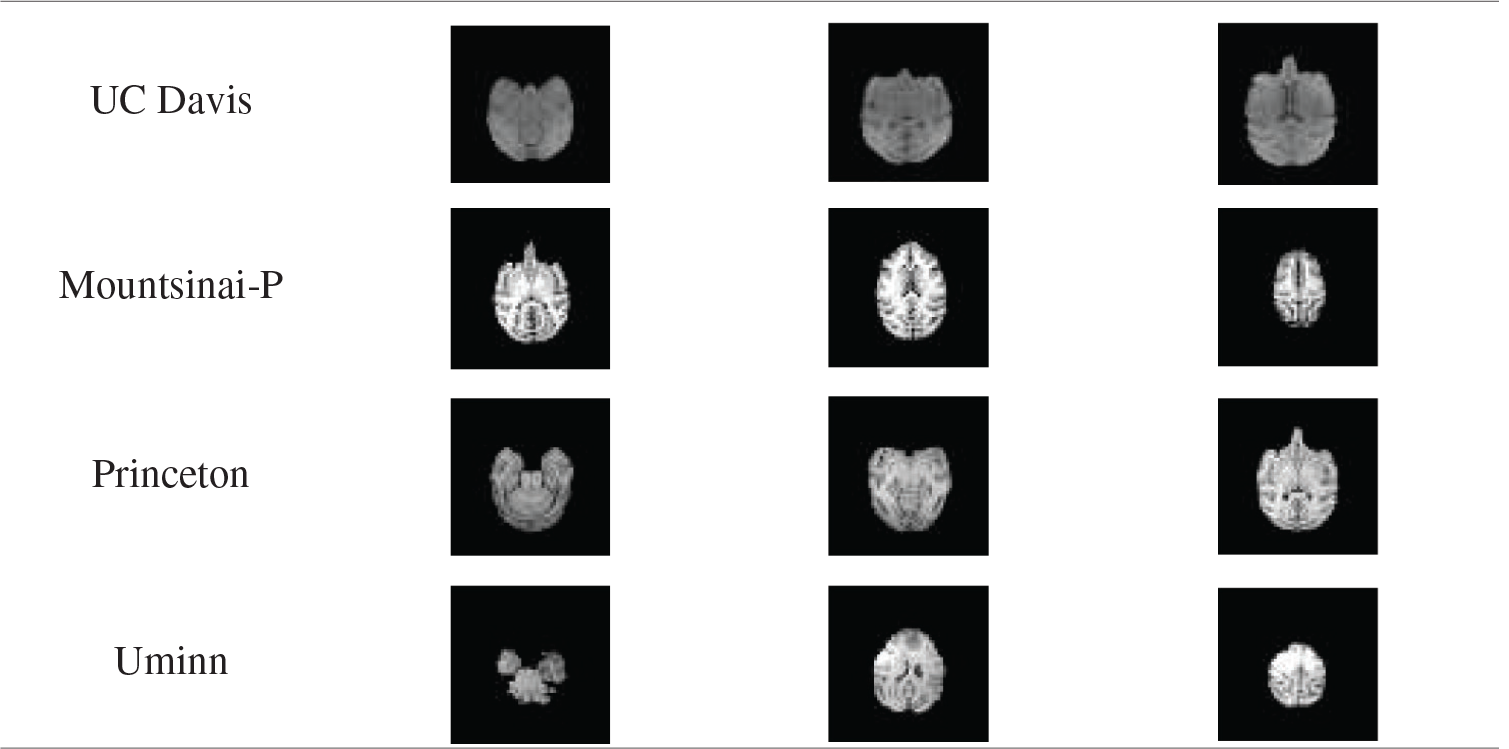

1. UC Davis Dataset. The data set collected data from 19 rhesus monkeys using the Siemens Skyra3T scanner. The data included structures T1 and T2, as well as task-state fMRI and dMRI. In this experiment, NMR data with structures T1 were used. All the 19 monkeys were females, ranging in age from 18.5 to 22.5 years. The weight distribution was 7.28-14.95kg. Scanning sequence parameters: voxel resolution = 0.3 × 0.3 × 0.3 mm, TE = 6.93 ms, TR = 15 ms, TI = 1100 ms, Flip Angle = 8°.

2. Mountsinai-P Dataset. Data of 9 macaques were collected by the Philips 3T scanner. The data included structures T1, T2, and dMRI. In this experiment, NMR data with structures T1 were used. The data set included 8 males and 1 female, with an age distribution of 3.4-8 years and a weight distribution of 4.7-7.42kg. The scanning sequence parameters were as follows: voxel resolution = 0.5 × 0.5 × 0.5 mm, TE = 6.93 ms, TR = 15 ms, TI = 1100 ms, Flip Angle = 8°.

3. Princeton Dataset. The data set used Simens Prisma VE11C 3T scanner to collect data from two rhesus monkeys. The data included structures T1, T2, dMRI, and task-state fMRI. In this experiment, NMR data with structures T1 were used. All the two macaques in the data set were male, with an age distribution of 3 years and a weight distribution of 4.7-5.5kg. Scanning sequence parameters were as follows: voxel resolution = 0.5 × 0.5 × 0.5 mm, TE = 2.32 ms, TR = 2700 ms, TI = 850 ms, Flip Angle = 9°.

4. Uminn Dataset. The data set was used to collect the data of 2 rhesus monkeys with Simens 7T scanner. The data included structures T1, T2, dMRI, and task-state fMRI. In this experiment, NMR data with structures T1 were used. All the two macaques in the data set were female, and their age distribution was over 10 years old. The scanning sequence parameters were as follows: voxel resolution = 0.3 × 0.3 × 0.3 mm, TE = 3.65 ms, TR = 2500 ms, TI = 1100 ms, Flip Angle = 7°.

Experiment one: The ce-LevelSet of the model in this paper was applied to UC Davis, Mountsinai-P, Princeton and Uminn, respectively, to verify the feasibility of the model in this paper. The default parameters of the model in this paper are: time step

Tab. 5 shows the results of monkey brain tissue extraction after the model was applied to four sets of UC Davis, Mountsinai-P, Princeton and Uminn, and it can be found that the model applied to four different data sets in this paper can achieve complete extraction of monkey brain tissue, with good extraction effect.

Tab. 6 shows the average value of DSC and JS of rhesus monkey brain tissue obtained after the model is applied to four data sets. From Tab. 6, it can be found that the monkey brain extraction results obtained after the model is applied to different data sets are good, and the similarity of DSC and JS with the standard brain tissue can reach about 0.75, and the performance is stable.